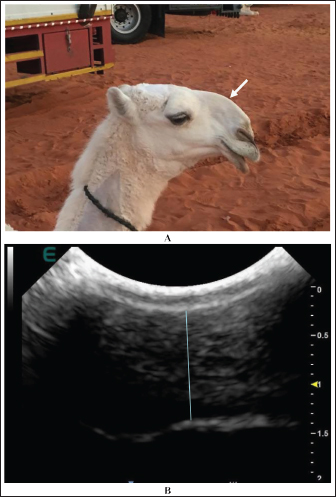

Extension and stretching of the lips in camels due to daily massage of the lips and sometimes binding with a rubber band resulted in blood congestion and lip enlargement (Fig. 7). Radiographic evaluation of filler materials in the perinasal region showed swelling of the soft tissues to the extent of variable degrees owing to the injected fillers; the injected substances appeared gray and had a soft tissue density (Fig. 8). In the injected lips, the injected filler was hypoechoic, and the scanning manner of the injected lips appeared heterogeneous (Fig. 9). In the perinasal area, the filler material appeared as either hypoechogenic or anechoic spots (Fig. 10). In infrared thermography (IRT), stretched lips appeared lighter and more heterogeneous than the darker and homogenous lips of healthy camels. In addition, the injected lip sites appeared darker than the surrounding tissue as their temperature was relatively higher when compared with healthy non-injected lip tissue (Fig. 11). Figure 12 shows a camel with enlargement of the lips due to filler injection, while Figure 13 shows enlargement of the soft palate or dulla and clitoris due to testosterone hormonal injection.

Fig. 10. Enlargement of the perinasal area in a female camel due to injection of filler material (white arrow) (A). Image (B) shows the ultrasonographic detection of the injected filler material (blue line) that appeared hypoechoic with anechoic spots.

Fig. 11. Injection points (1, 2, 3) of the lips in a female camel using filler material (a). Image (b) shows the detection of the three injected points by thermography.